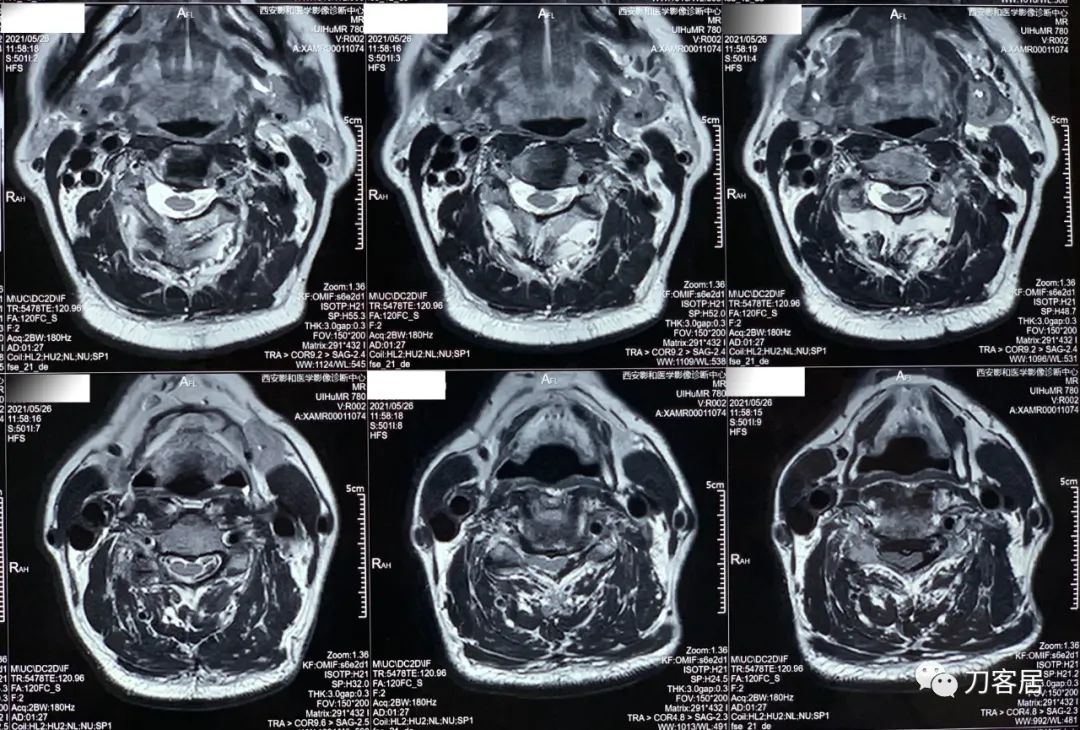

20210526-颈椎MRI经椎间盘横截面扫描。